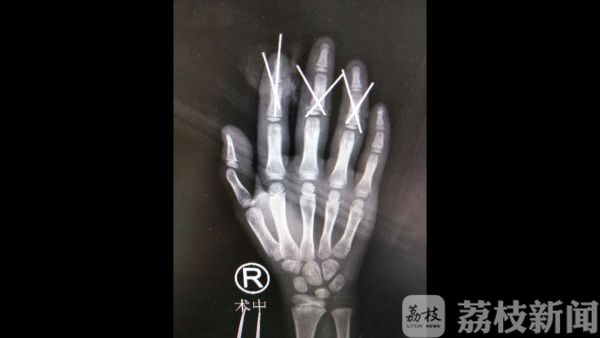

事发后家长第一时间送医,由于断指保存完好,小蕊在经历了近8个小时的手术后,4根断指被成功再植。目前,小蕊正处在术后恢复阶段,后期还需要接受一些康复治疗。

医生表示,孩子将来大部分工作都能做,只是手指每个关节的活动度会受一些影响。